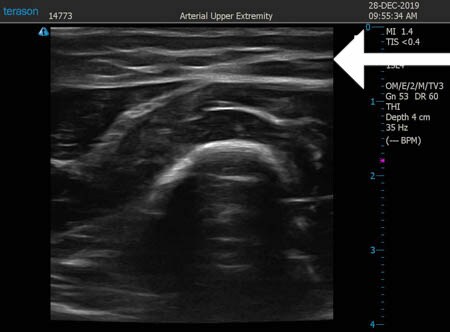

同様に左二の腕 ↓ ↓ ↓

↓ ↓ ↓

左ちからこぶ